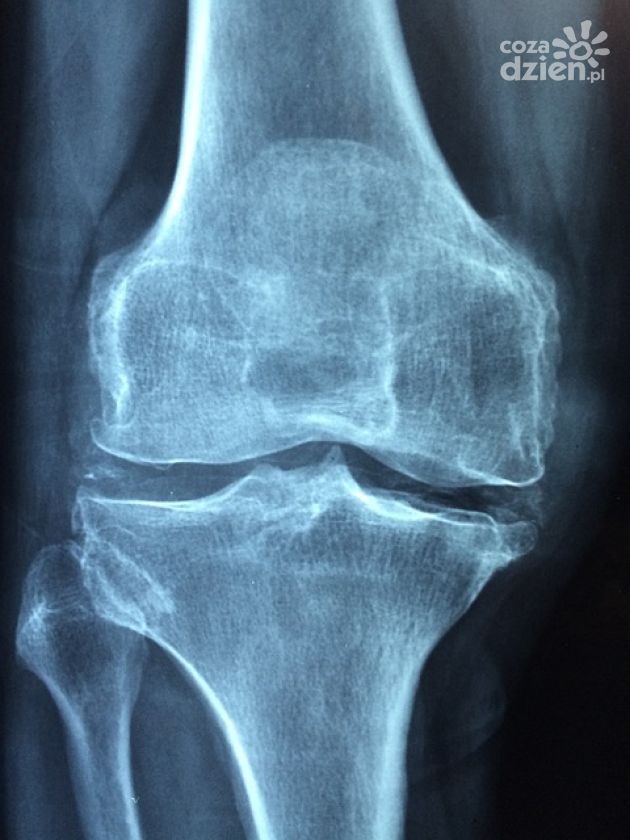

USG ortopedyczne to jeden z najważniejszych rodzajów badań ultrasonograficznych. Wśród części ciała, które najczęściej poddawane są badaniu USG wymienić należy przede wszystkim kolano. Dzięki tej technice można zdiagnozować schorzenia zlokalizowane w kłykciach kości udowej, stawie skokowym lub np. uszkodzenie łąkotki.

Badanie USG umożliwiają precyzyjną ocenę struktur anatomicznych stawu kolanowego. To okazuje się szczególnie istotne w przypadku podejrzenia urazów, chorób zwyrodnieniowych czy innych dolegliwości powodujących ból kolan. Badania tego typu są szybkie i bezbolesne dla pacjenta, jednocześnie pozwalając na wczesne zdiagnozowanie różnych zmian i tym samym wprowadzenie odpowiedniego leczenia. Na czym jednak polega badanie ultrasonograficzne? Kiedy powinno być przeprowadzone? Omawiamy to w nowym artykule.

USG kolana to badanie obrazowe wykorzystujące fale dźwiękowe do uzyskania uzyskania wglądu w stawu kolanowego. Pozwala na wydajną ocenę różnych struktur anatomicznych - przede wszystkim kości, chrząstek, ścięgien, więzadeł oraz torebki stawowej. Decyzję o jego przeprowadzeniu lekarz podejmuje przede wszystkim w następujących przypadkach:

Słowiem podsumowania - USG kolana to bezpieczne badanie, dzięki któremu lekarzom może szybko postawć trafną diagnozę i na tej podstawie zalecić odpowiednie leczenie. Dzięki zaawansowanej technologii ultrasonograficznej, badanie to umożliwia dokładne zobrazowanie struktur w obrębie kolana i tym samym wykrycie różnego typu urazów, chorób takich jak lateralizacja rzepki, stanów zapalnych, a nawet nowotworów.